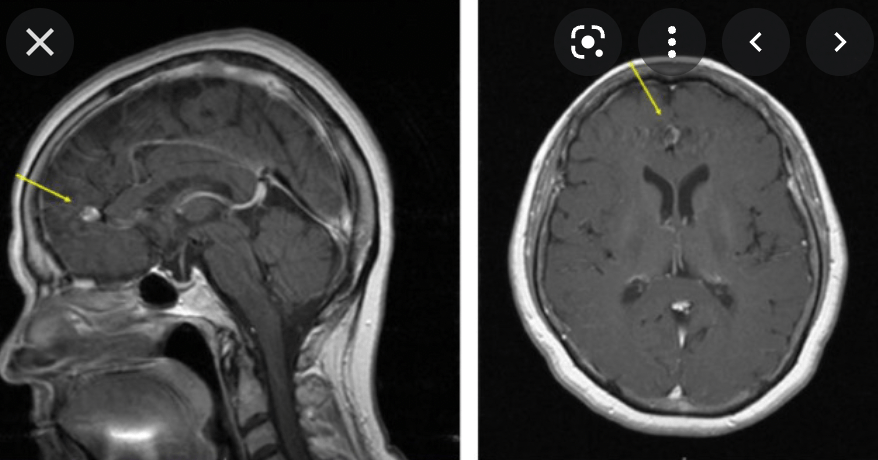

Stroke patient's MRI is shown below. What are the likely artery blocked, brain area affected and symptoms of presentation?

Anterior cerebral artery, frontal lobe and altered mental status, impaired judgement, contralateral weakness, contralateral cortical sensory deficits, urinary incontinence